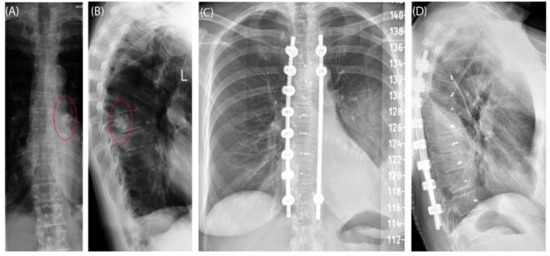

Case 3 involved a 63-year-old female patient with a diagnosed inner thoracic chondrosarcoma (G2) of the 9th left rib. The soft tissue component extended from the 7th to the 11th rib next to the aorta and lungs (Figure 5). After CT-MRI fusion and planning, marginal resection was possible by combining a partial corpectomy T7–T11 with laminectomy T7–T11 and partial resection of ribs 7–11 on the left side. Reconstruction was carried out by instrumentation spondylodesis with a screw-rod system from T5-T11 and extensive coverage with bovine pericardium (Baxter, Deerfield, IL USA) (Figure 6). The postoperative histopathological examinations confirmed tumor-free resection margins and revealed a high-grade tumor (G3). After adjuvant radiation and a four-month postoperative follow-up, there was no sign of local recurrence. The patient returned to daily life without any sensomotoric deficit.

Figure 6. Case 3: Preoperative radiographs in frontal (A) and lateral (B) views, red circles indicate the bony tumor mass; postoperative radiographs in frontal (C) and lateral (D) views.